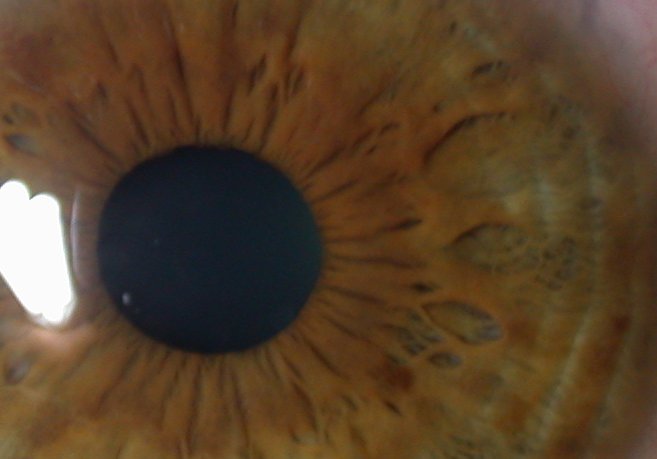

Iridology is the study of the irises of the eyes as maps of the entire body. It is a non-invasive assessment of certain aspects of health.

It shows inherited strengths and weaknesses

as well as some acquired traits, areas of relative over and under-function and as such can try to assess areas where things could be optimised.

The diagram above is an example chart of the areas of the iris of the right eye (a mirror image chart relevant if you are looking in a mirror). There is a lot of close up detail contained within the iris including possible fibre anomalies, pigments, whitening and shape variations of the structures it contains. Sclerology is a similar study of the blood vessels, colours and patches of the whites of the eyes which adds more information to that obtained from iridology.